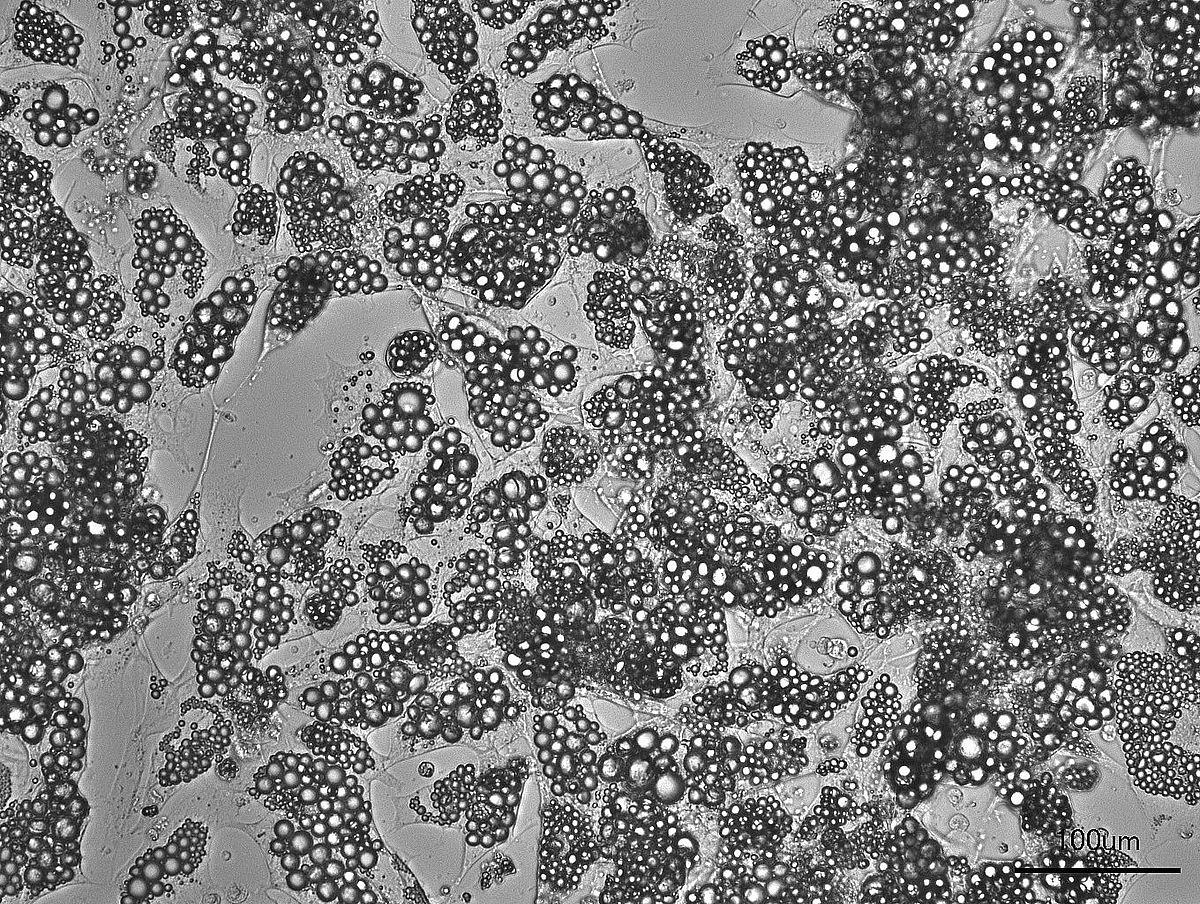

Die Forschenden analysierten genetische Sequenzen von 7719 Menschen mit extremer frühkindlicher Adipositas. Bei 316 Personen und 461 ihrer Familienmitglieder wiesen sie Veränderungen in MC4R nach. Der Vergleich mit Daten von mehr als 330 000 Kontrollpersonen ohne solche Veränderungen zeigte: Trotz eines ähnlich hohen Body-Mass-Index hatten die Betroffenen deutlich bessere Blutfettwerte und einen niedrigeren Blutdruck. Insbesondere bei Erwachsenen mit MC4R-Veränderungen waren die Werte für Gesamtcholesterin, das »schlechte« Low-Density-Lipoprotein-Cholesterin und Triglyzeride signifikant niedriger. Die Wissenschaftlerinnen und Wissenschaftler untersuchten auch, wie sich der Stoffwechsel von Personen mit MC4R-Defekt nach einer fettreichen Mahlzeit verhält. Sie fanden Hinweise darauf, dass bei Betroffenen im Vergleich zur Kontrollgruppe mehr Fett im Fettgewebe gespeichert wird, was die niedrigeren Fettstoffwechsel-Werte im Blut erklären könnte.